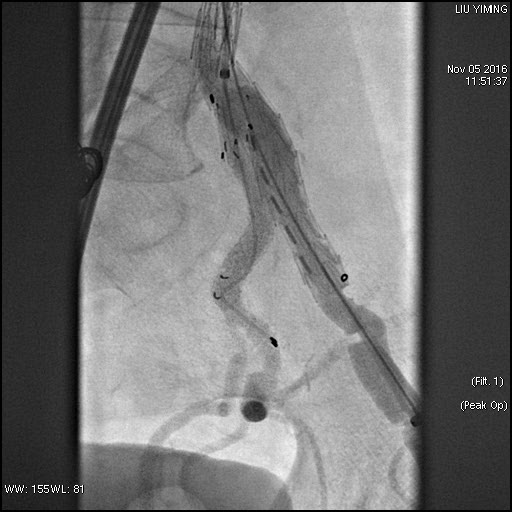

其中,在复杂主动脉病变腔内修复术应用手术直播中,郭伟教授带领其团队使用先健科技公司的髂动脉分叉支架系统(IBD)以完全腔内重建的方式成功修复复杂腹主动脉瘤及髂动脉瘤。该例手术患者为64岁的男性,被诊断为肾下腹主动脉瘤,瘤体最大直径约6.5cm,双侧髂动脉瘤。患者成功植入先健科技IBD支架,定位准确,无内漏,成功保留了左侧髂内动脉,术后造影显示髂内动脉通畅。

图:术前造影、术中造影、术后造影